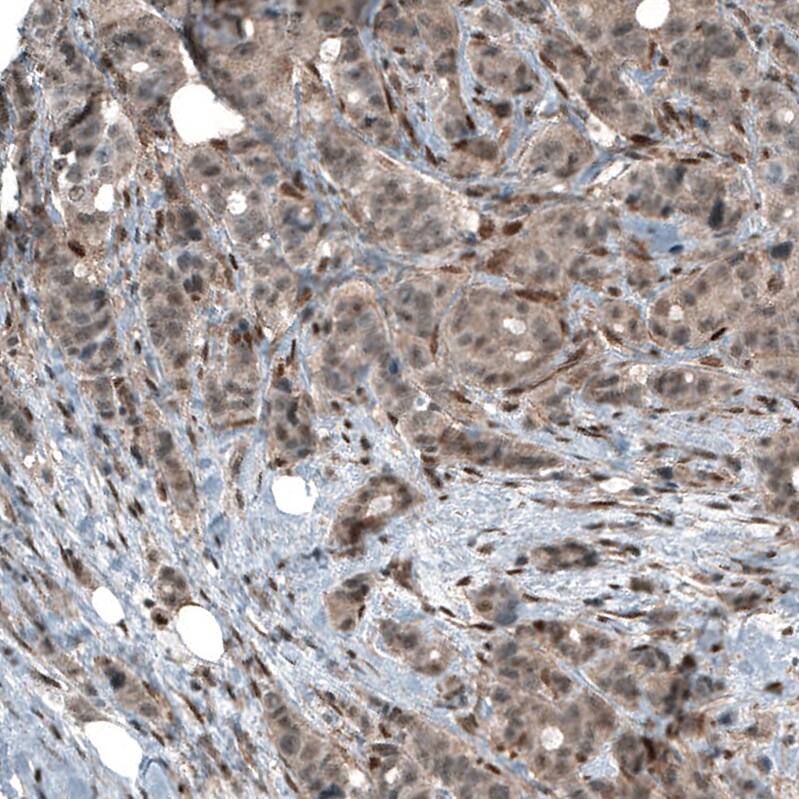

Staining of human breast cancer shows moderate cytoplasmic positivity.

Staining of human Fallopian tube shows strong cytoplasmic and nuclear positivity in glandular cells.

Staining of human pancreas shows low cytoplasmic positivity in exocrine glandular cells as expected.

Staining of human tonsil shows moderate cytoplasmic positivity in germinal center cells.

Staining of human testis shows weak to moderate cytoplasmic and nuclear positivity in cells in seminiferous ducts.